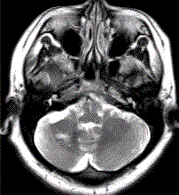

问题 患者女,41岁。头痛半年,加重10d。头部MRI显示如下图。 关于该病的MRI描述正确的是

选项 A.右侧小脑半球圆形长T2信号影,病变周边可见环形低信号 B.病变周边环形低信号对病变的诊断价值不大 C.病变邻近右侧小脑半球可见一条形高信号,其对病变的诊断价值不大 D.病变邻近右侧小脑半球可见一条形高信号,其对病变的诊断价值较大 E.第四脑室受压变窄对于病变的诊断价值较大 F.病变的内部信号不均匀对病变的诊断价值较大

答案 ADF